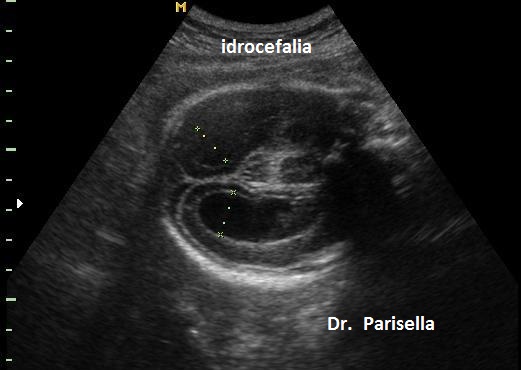

1. ventricolomegalia,